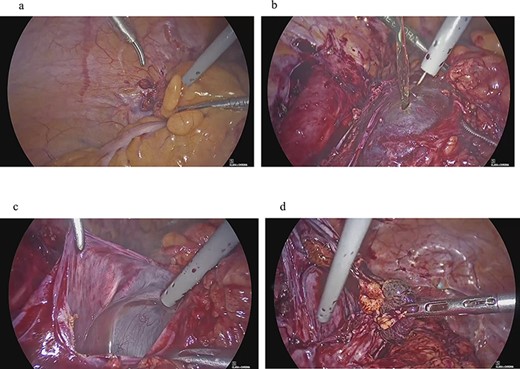

Clinical findings of case 2 (during surgery for PIC). (a) Strong adhesion between the sigmoid colon and pelvic wall in the left adnexal region. (b) When the sigmoid mesentery and left pelvic peritoneum were removed and the cyst was opened, a yellow transparent liquid was ejected. (c) The cavity formed by adhesions. (d) Left ovarian tissue inside PIC.

Four years and 6 months after surgery, she presented with lower left abdominal pain. A multilocular cyst, measuring ~10 cm, was detected on the vaginal stump by transvaginal US (Fig. 2b). Since the cyst was considered to be causing her symptoms, emergency surgery was performed. Adhesions were observed in the left adnexal region, and a clear yellow liquid was retained in the cavity formed by the adhesions (Fig. 3). The adhesions were removed by laparoscopic surgery and left adnexal excision was performed, which ameliorated her symptoms.